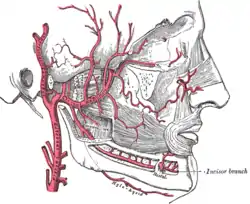

Mandible. Inner surface. Side view. Plan of branches of internal maxillary artery.

Plan of branches of internal maxillary artery. Distribution of the maxillary and mandibular nerves, and the submaxillary ganglion.